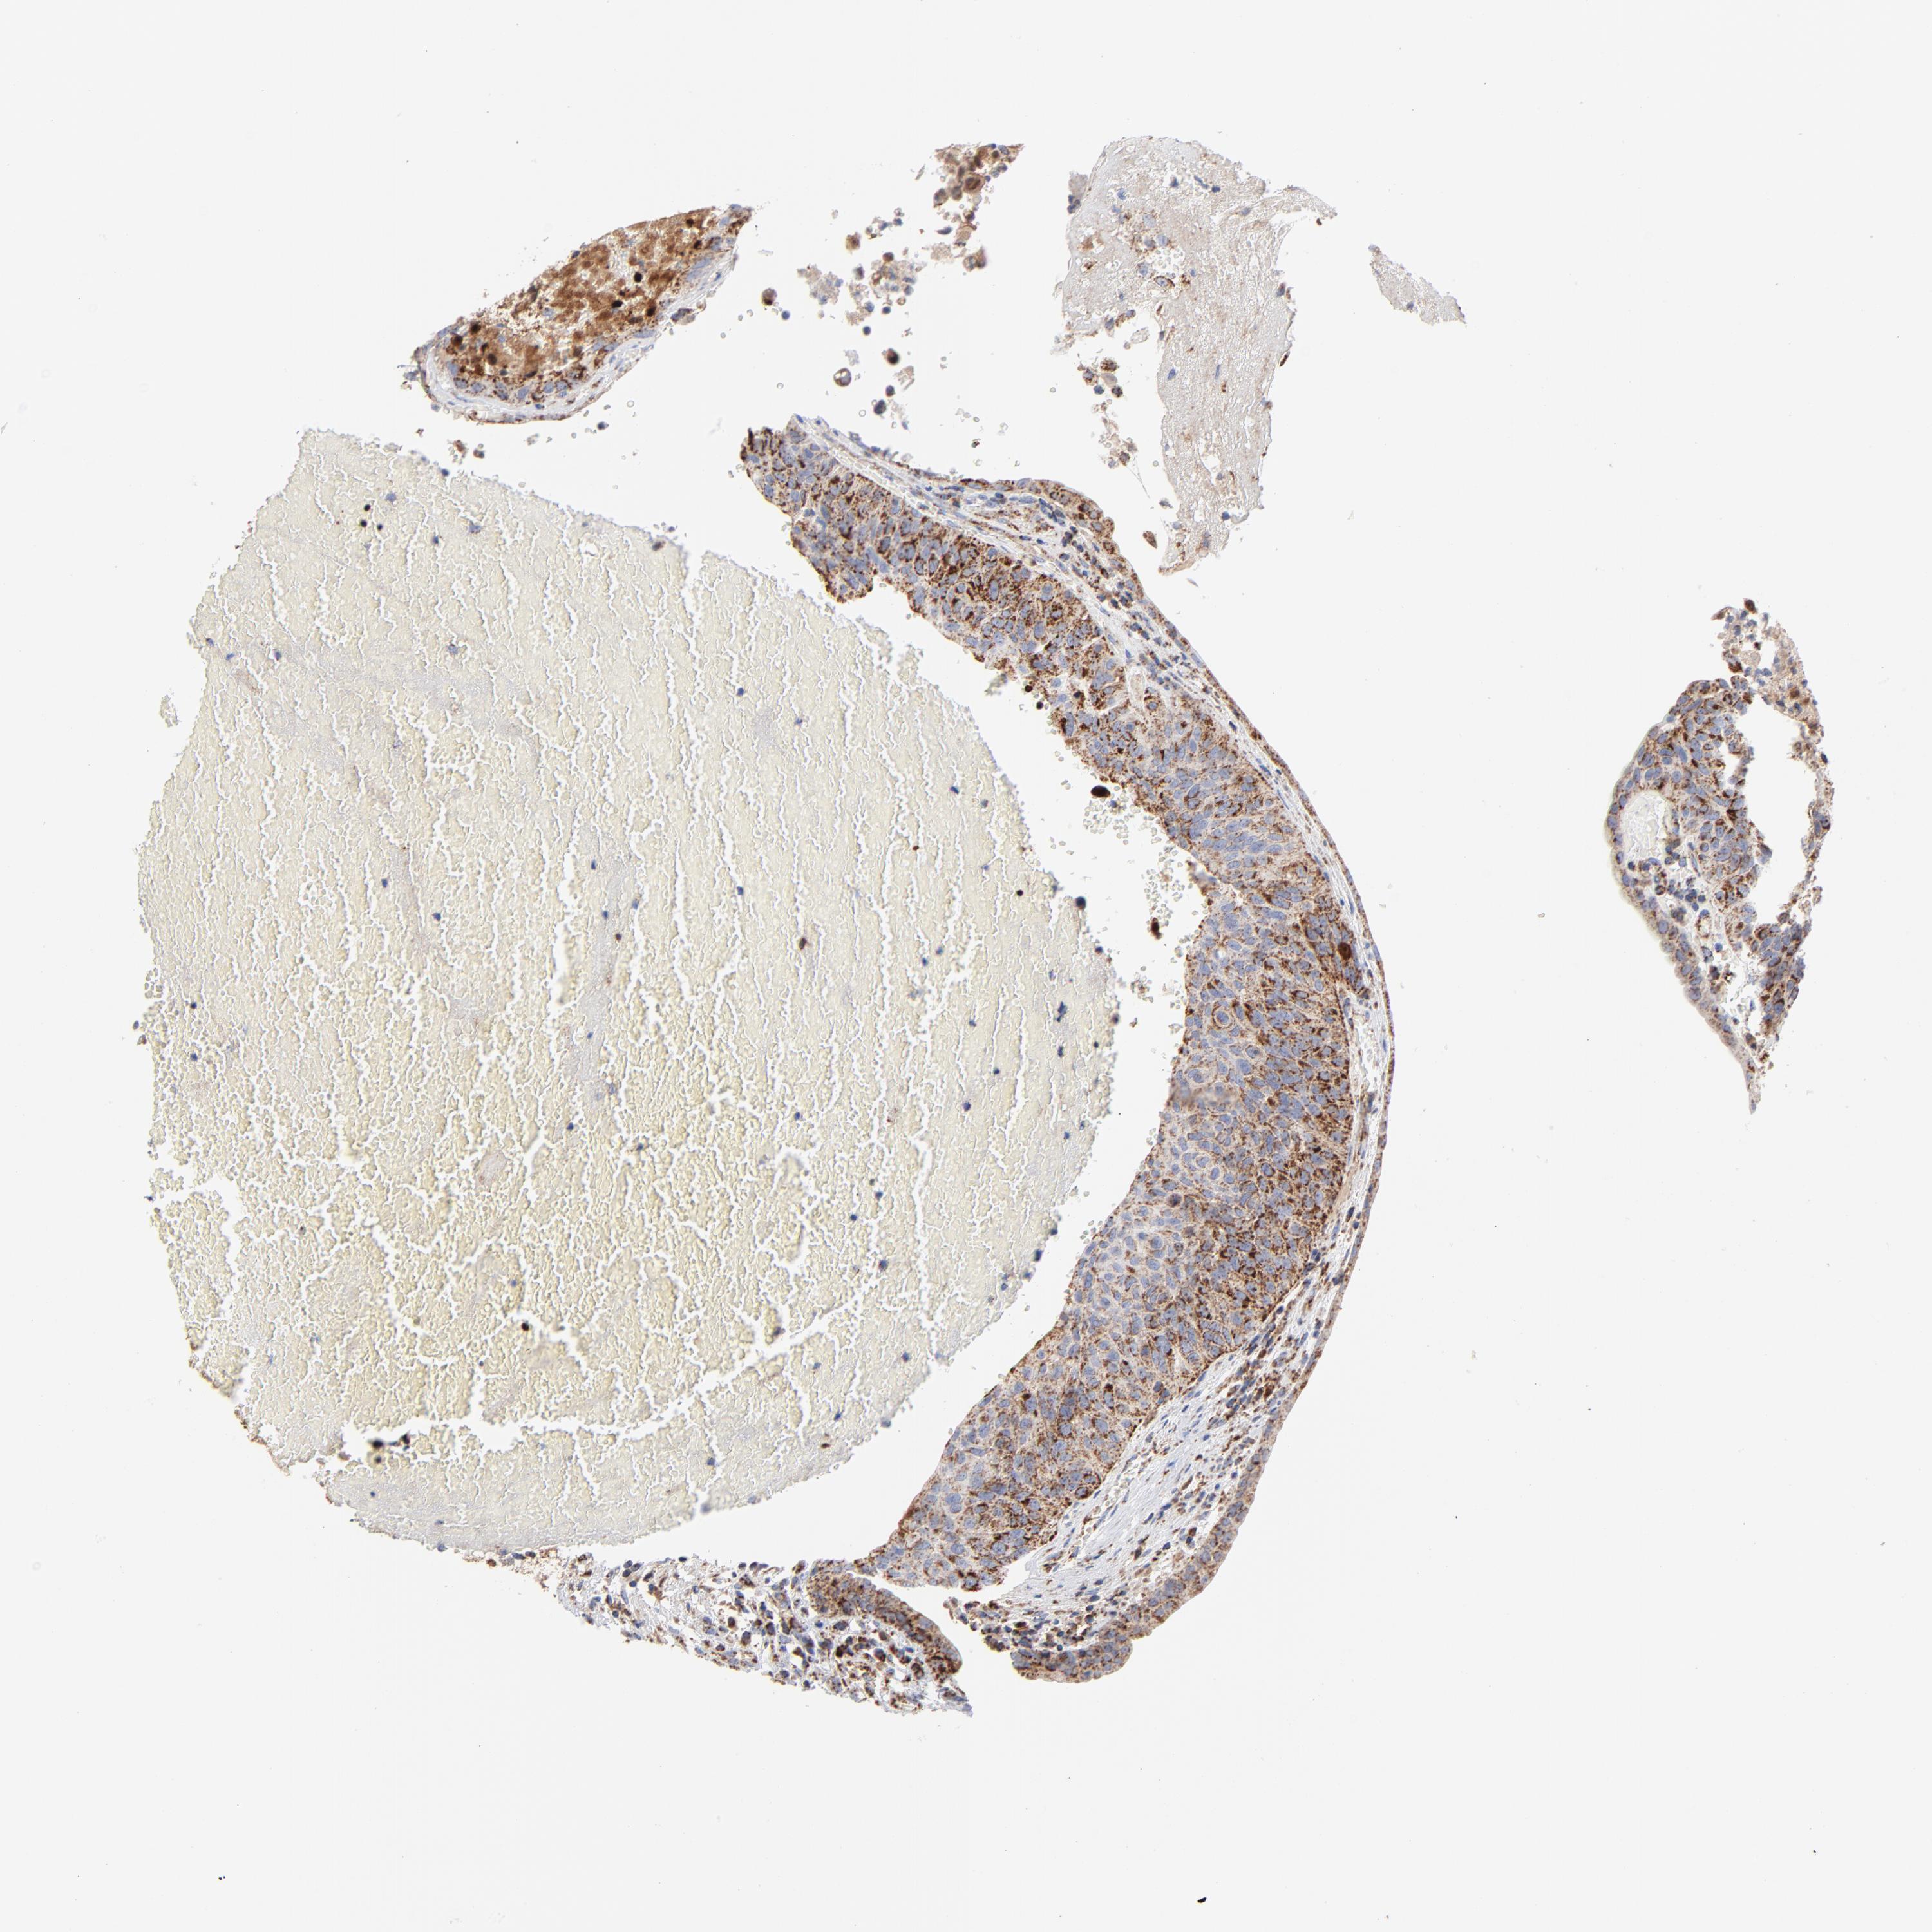

UROTHELIAL CANCER - Protein expressioni

A mouse-over function shows sample information and annotation data. Click on an image to view it in a full screen mode. Samples can be filtered based on level of antibody staining by selecting one or several of the following categories: high, medium, low and not detected. The assay and annotation is described here.

Antibody stainingi

Antibody staining in the annotated cell types in the current human tissue is reported as not detected, low, medium, or high, based on conventional immunohistochemistry profiling in selected tissues. This score is based on the combination of the staining intensity and fraction of stained cells.

Each image is clickable and will lead to virtual microscopy that enables deeper exploration of all samples and also displays staining intensity scores, fraction scores and subcellular localization as well as patient and tissue information for each sample.

Antibody HPA001825

Antibody CAB003857

Staining

High

Medium

Low

Not detected

Intensity

Strong

Moderate

Weak

Negative

Quantity

>75%

75%-25%

<25%

None

Location

Nuclear

Cytoplasmic/membranous

Cytoplasmic/membranous,nuclear

Urothelial carcinoma, High grade

Urothelial carcinoma, Low grade